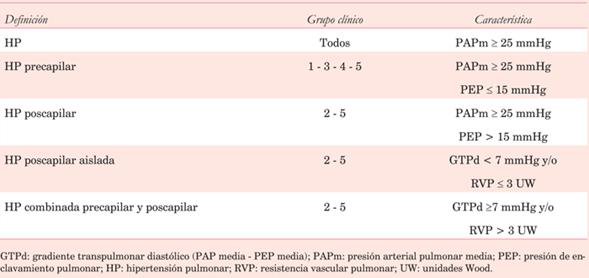

En el 6º Simposio Mundial de HTP5 se ha actualizado la clasificación clínica (tabla 1), agrupando los procesos y las enfermedades que la originan en cinco grupos que se diferencian por sus mecanismos fisiopatológicos, presentación clínica y opciones terapéuticas.

En la (tabla 2) se reúnen los diferentes tipos hemodinámicos junto a la correspondiente definición clínica. La enfermedad HTP inducida por ejercicio, no ha sido definida2. Las últimas guías recomiendan no utilizar este término debido a la falta de evidencia que demuestre a partir de qué valor de PAPm durante el ejercicio sobrevienen implicancias pronósticas6.